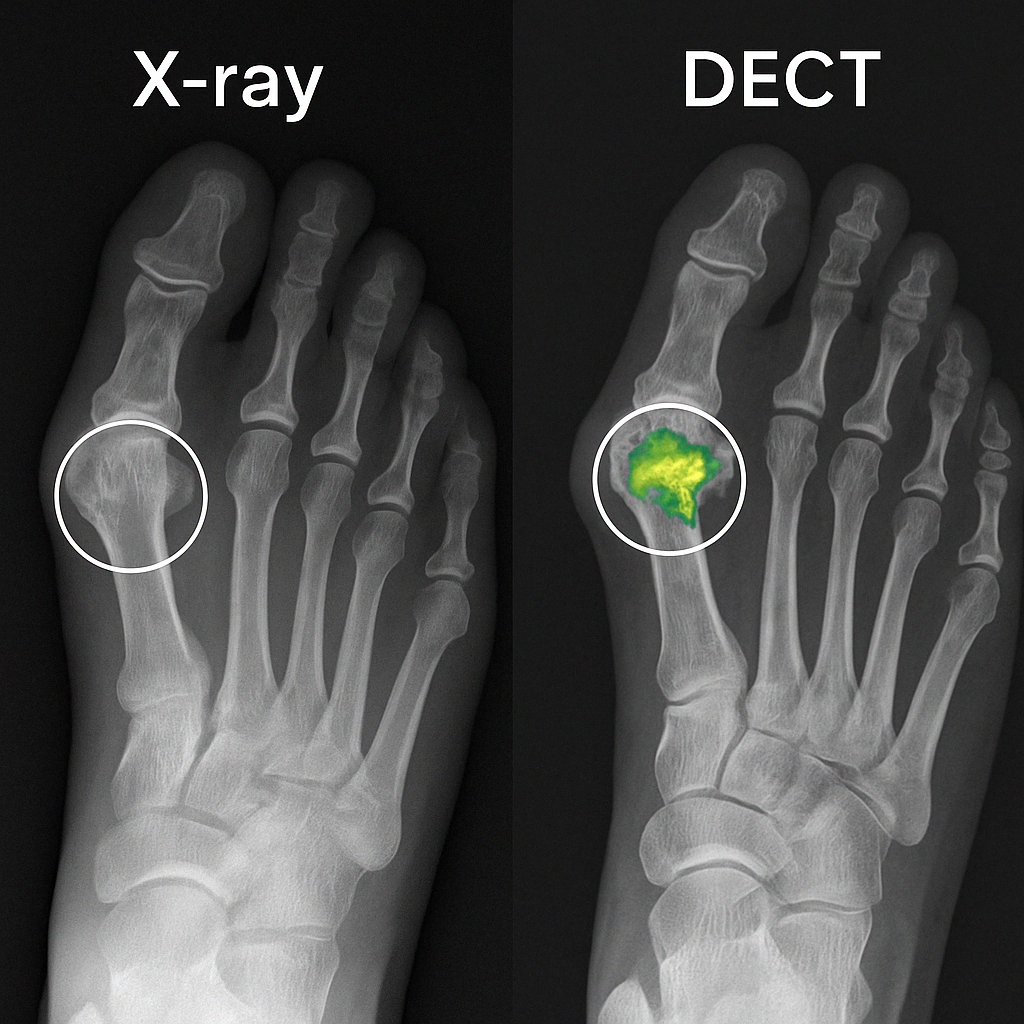

🔸 Dual-energy CT (DECT):

- 요산 결정만을 특정하게 시각화 가능

- 정확도 높고, 침범 범위 확인에 매우 유용

▶ DECT는 두 형태를 감별하는 데 매우 유용하며,

영상 진단과 임상 양상을 종합하여 통풍의 형태를 정확히 분류해야

맞춤형 치료가 가능합니다.